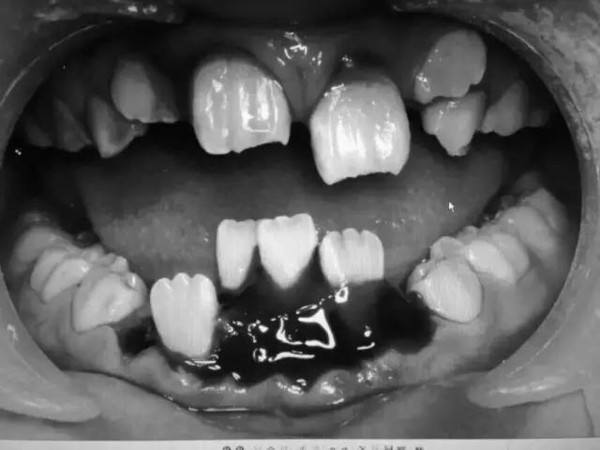

经过初步检查,琪琪牙龈外伤出血,乳牙脱落,上面2颗新换的门牙已经脱出牙槽窝,下面4颗新换的牙齿向舌侧倾倒,并伴有牙槽骨骨折。

处理牙外伤,最关键的是固定。通常是通过夹板、颌垫来固定松动牙,可孩子处于替牙期,口腔内情况复杂,既有即将脱落的乳牙又有新生的年轻恒牙。

乳牙的牙根和牙冠长度有限,不能满足固位要求,再加上牙槽骨骨折,牙龈撕裂伤严重,给本就复杂的治疗又增加了难度,只能通过牙龈悬吊外伤松动牙,初步稳固,再尝试固定。